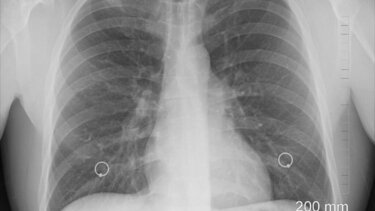

Η ερευνητική ομάδα χρησιμοποίησε αξονικές τομογραφίες περίπου 500 ασθενών με μεγάλους πνευμονικούς όζους για να αναπτύξει έναν αλγόριθμο τεχνητής νοημοσύνης με τη χρήση της ακτινολογίας. Η τεχνική μπορεί να εξάγει σημαντικές πληροφορίες από ιατρικές εικόνες που δεν εντοπίζονται εύκολα από το ανθρώπινο μάτι. Στη συνέχεια, το μοντέλο τεχνητής νοημοσύνης δοκιμάστηκε για να διαπιστωθεί αν μπορούσε να εντοπίσει με ακρίβεια τους καρκινικούς όζους.

Τα αποτελέσματα έδειξαν ότι το μοντέλο τεχνητής νοημοσύνης μπορούσε να προσδιορίσει τον κίνδυνο καρκίνου κάθε όζου με μεγάλη ακρίβεια (AUC 0,87). Σύμφωνα με τη μελέτη, το σύστημα θα πρότεινε την έγκαιρη παρέμβαση για 18 από τους 22 (82%) όζους που στη συνέχεια επιβεβαιώθηκαν ως καρκινικοί.